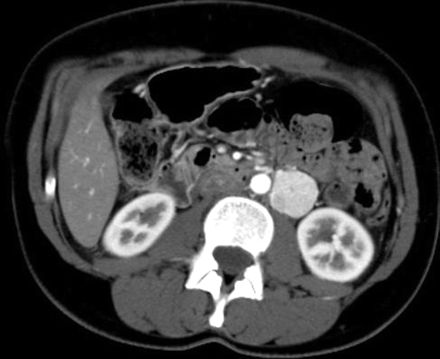

An 8 year boy was admitted with features of tuberculous meningitis. He was detected to have hypertension. Further investigations revealed an extra-adrenal paraganglioma. Tuberculous meningitis and paraganglioma could be chance associations. Paraganglioma is a rare and potentially lethal cause of secondary hypertension, very uncommon at this age. If left untreated it leads to complications arising from unrelenting hypertension. We report a case report on this very rare disease of paraganglioma presenting in an unexpected way.